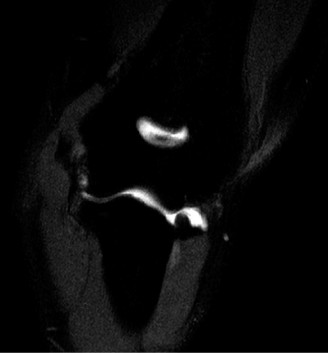

While plain films confirm the presence of osseous reactive changes, Magnetic Resonance Imaging (MRI) is indispensable for evaluating the articular cartilage, the integrity of the UCL, and the presence of occult loose bodies. A high-resolution MRI, preferably an MR Arthrogram (MRA) if subtle UCL pathology is suspected, provides a comprehensive map of the elbow's soft tissue envelope.

In this case, the MRI demonstrates focal chondromalacia and subchondral edema at the posteromedial olecranon tip and the corresponding medial wall of the olecranon fossa—the classic "kissing lesion" of VEO. Crucially, the anterior bundle of the UCL appears continuous and intact, with no evidence of high-grade partial tearing, T-sign (contrast leakage beneath the distal insertion), or severe attenuation. The flexor-pronator mass and the ECRB origin are pristine.

For definitive surgical planning, particularly when addressing complex osseous impingement, a non-contrast Computed Tomography (CT) scan with 3D reconstructions is often utilized. The CT scan allows the orthopedic surgeon to precisely quantify the size and exact location of the posteromedial osteophyte.

Surgical templating is critical here. The surgeon must calculate exactly how many millimeters of bone need to be resected to alleviate the impingement without violating the native olecranon anatomy. Resecting too much bone—specifically, violating the medial cortex of the olecranon—can inadvertently increase strain on the UCL, leading to iatrogenic valgus instability. The CT scan provides the exact topographical map required to execute a precise, conservative arthroscopic resection.